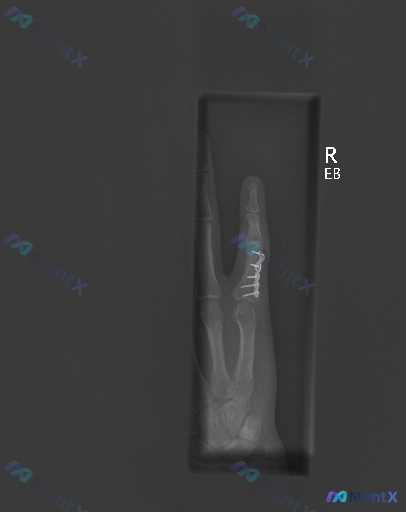

右示指近节指骨骨折术后X光片,未见明显骨质破坏就可以放心了吗?

整理到一份右示指近节指骨骨折术后的X光随访资料,先不说临床背景,只看影像描述,大家第一感觉怎么样? 影像核心发现: - 右手示指近节指骨可见金属钢板及螺钉固定,位置良好 - 钢板覆盖区域因金属伪影遮挡,原始骨折线愈合情况难以清晰评估 - 未遮挡区域骨皮质连续性尚可,关节间隙正常,未见明显骨质破坏或脱...